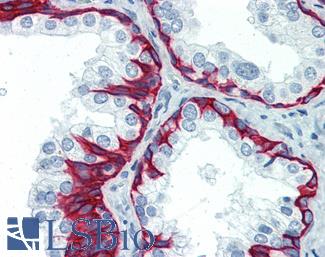

SMMHC

Anti-Myosin, Smooth Muscle Heavy Chain antibody IHC of human prostate. Immunohistochemistry of formalin-fixed, paraffin-embedded tissue after heat-induced antigen retrieval. Antibody LS-B5148 concentration 20 ug/ml.